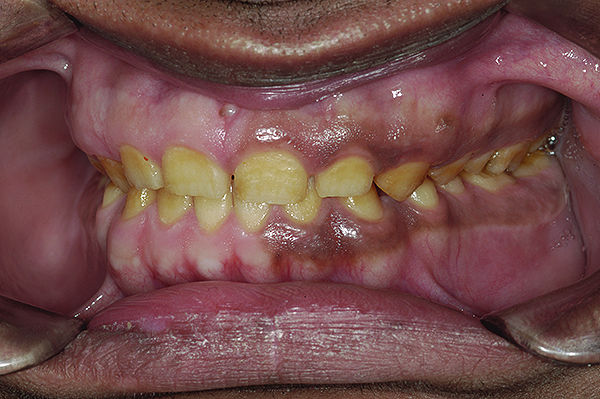

The authors report on a 21-year-old patient who presented with severe discoloration and mild sensitivity of teeth (Figure 1). The teeth visible in his smile were very short, unsightly, and unbecoming for his age.

A thorough clinical examination and analysis were carried out to assess the esthetic and functional problems of the patient (Figure 2 through Figure 7). The medical history was non-contributory, except for mild leukoderma. Temporomandibular joint (TMJ) function was within normal range.

Figure 2. Preoperative 1:2 retracted frontal view.

Figure 2

Figure 5. Preoperative 1:1 retracted frontal view.

Figure 5